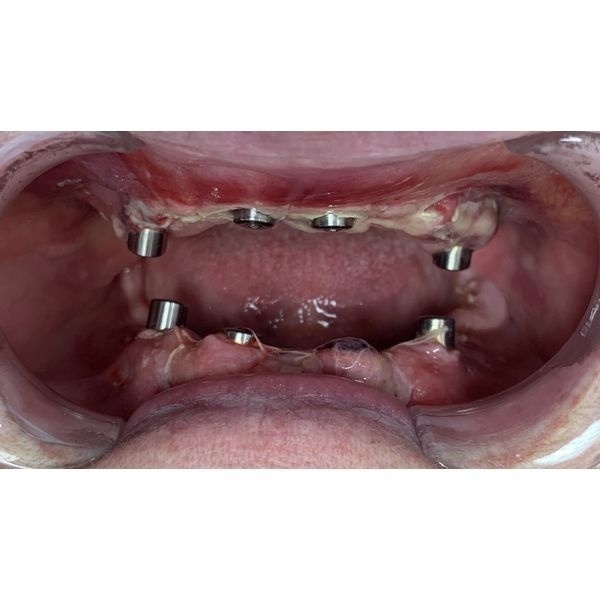

- сделали инфильтрационную анестезию;

- удалили зубы;

- одномоментно установили импланты в область ранее удалённых зубов на обеих челюстях;

- зафиксировали на имплантах мультиюниты, которые позволят прикрепить протезы с помощью винтов;

- сняли слепки с обеих челюстей для изготовления временного несъёмного зубного протеза на винтовой фиксации.

Уже на следующий день после операции женщина смогла забрать свой протез.